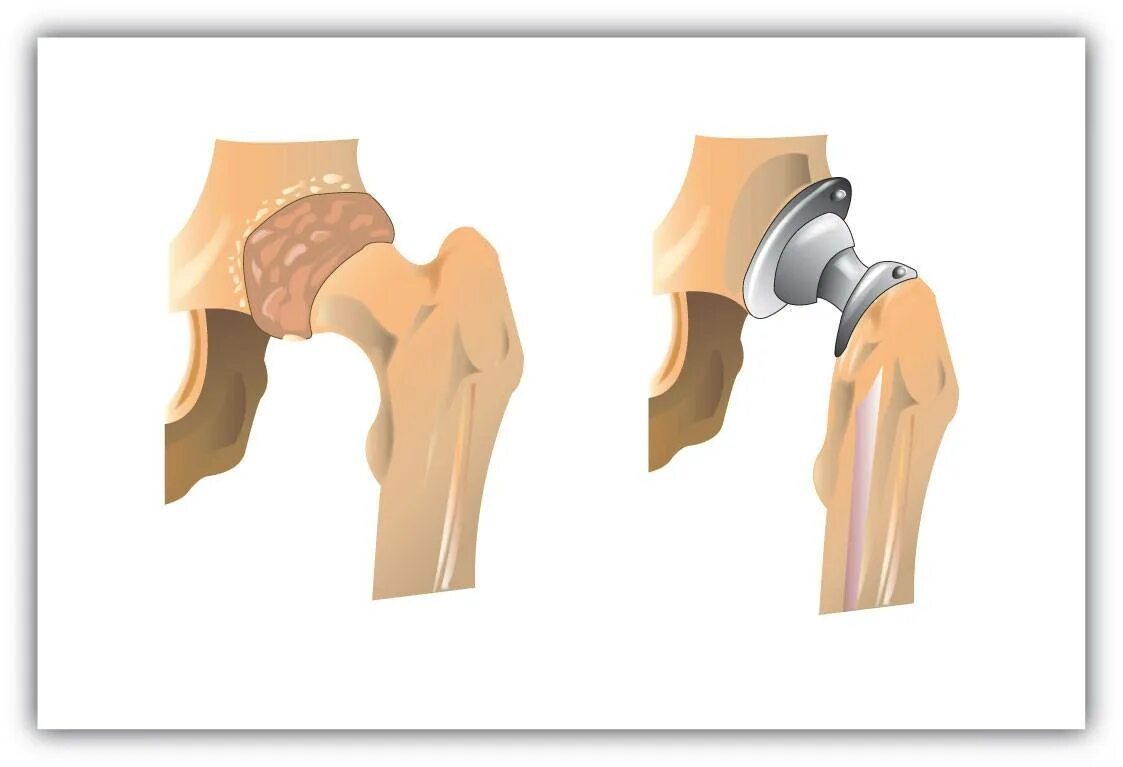

Болезнь бехтерева тазобедренных суставов